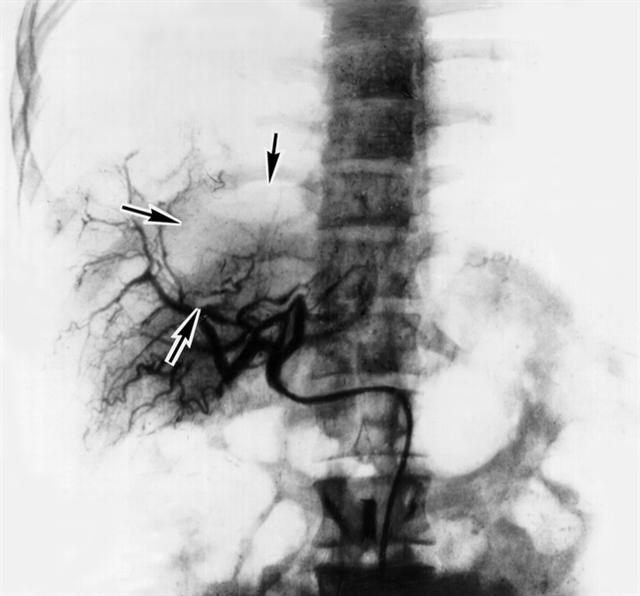

Рис. 5. Селективная ангиогепатограмма при альвеолярном эхинококкозе печени: стрелками указана васкулярная зона в области паразитарного узла.